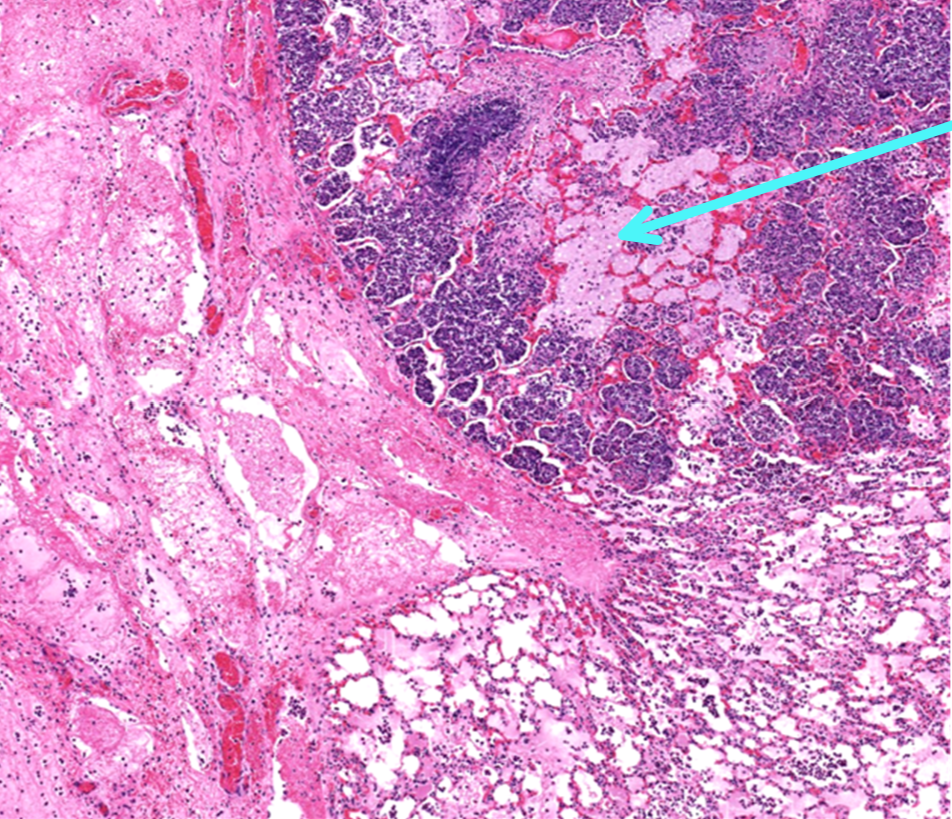

This is a slide from a bovine lung.What would the cellular exudate be composed of in this lesion?

A

macrophages, neutrophils, and necrotic alveolar epithelium

This is from a bovine lung. What is the histomorphologic diagnosis for this lesion?

acute fibrinopurulent bronchopneumonia

Why would this lesion be acute?

because the exudate is predominantly neutrophils and fibrin

Q

Identify this structure:

interlobular lymphatics with fibrin and hemorrhage